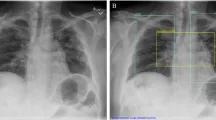

Введение в исследование ИИ в радиологии

Количество программных приложений с искусственным интеллектом (ИИ) для радиологии быстро растёт. На данный момент существует более 190 продуктов с маркировкой CE, из которых почти 100 получили разрешение FDA класса II или III. Для рентгенографии грудной клетки — самого часто выполняемого рентгенологического исследования в мире — существует широкий спектр сертифицированных систем поддержки клинических решений с ИИ на рынке.

В исследовании участвовали 223 врача с разным уровнем экспертизы. Врачи внутренних болезней и неотложной медицины были классифицированы как нетask experts (неспециалисты в задаче), а радиологи — как task experts (эксперты в задаче). Участники получали рентгеновские снимки с точными диагностическими рекомендациями и должны были поставить диагноз, оценить качество совета и уверенность в своём решении.

- Объяснимость совета: визуальные аннотации на рентгеновских снимках или их отсутствие

Нетask experts показали значительное улучшение точности диагностики при получении аннотированных советов от ИИ. Врачи оценивали качество советов ИИ выше, чем человеческих советов. На уверенность в диагнозе манипуляции не оказали сильного влияния.

Получение аннотированного совета от ИИ привело к наивысшей диагностической точности как у нетask experts, так и у task experts

Нетask experts значительно выиграли от аннотаций, в то время как для task experts эффект был статистически незначимым. Это может быть связано с ceiling effects — изначально высокой точностью радиологов.